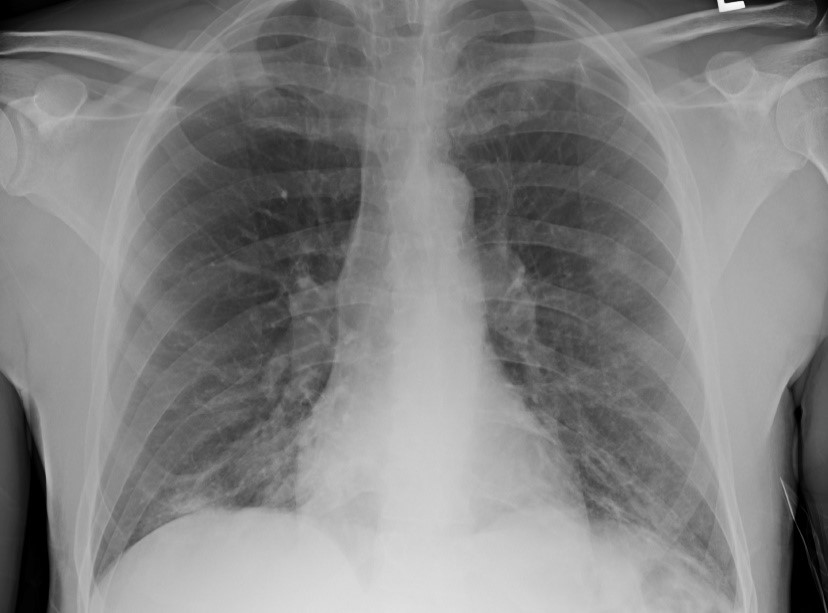

A 65-year-old man with no significant medical history presented to the emergency department to which he had been sent from an outside facility to rule out tuberculosis. His primary concern was back pain. ...